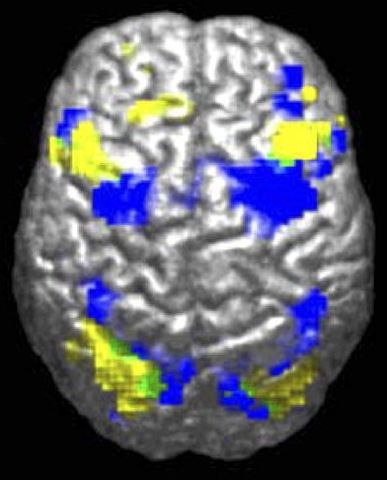

English: fMRI-derived image of difference between brains of autistic and control groups. Legend reads "Activation during visuomotor coordination: Autism Group [yellow], Control Group [Blue], Overlap (both groups) [green]". for Laurent Mottron*, "Even researchers who study autism can display a negative bias against people with the condition. For instance, researchers performing functional magnetic resonance imaging (fMRI) scans systematically report changes in the activation of some brain regions as deficits in the autistic group — rather than evidence simply of their alternative, yet sometimes successful, brain organization". * Laurent Mottron, Changing perceptions: The power of autism ; Nature 479, 33–35 (03 November 2011) ; doi:10.1038/479033a En ligne : 2011-11-02

Français : Imagerie IRMf montrant les différences d'activité du cortex cérébral lors d'une activité de coordination visualo-motrice chez des personnes autistes et appartenant à des groupes-témoin. Les zones activées apparaissent jaunes pour le groupe des autistes [bleu pour le groupe de contrôle et vert quand elle est la même pour les deux groupes. Pour Laurent Mottron, neuropsychiatre et spécialiste de l'Autisme, les différences d'activation de certaines régions du cerveau montrées par l' imagerie par résonance magnétique fonctionnelle (IRMf) pourraient ne pas être seulement à considérer comme une preuve d'un trouble du fonctionnement du cerveau, mais aussi la preuve d'une organisation alternative du cerveau (observée comme efficace, par exemple lors de tests d' intelligence non-verbale).(Source : Laurent Mottron, Changing perceptions: The power of autism ; Nature 479, 33–35 (03 November 2011) ; doi:10.1038/479033a En ligne : 2011-11-02)

Figure 1A of: Powell K (2004). " Opening a window to the autistic brain". PLoS Biol 2 (8): E267. DOI: 10.1371/journal.pbio.0020267. PMID 15314667. PMC: 509312. |

Ralph-Axel Müller |